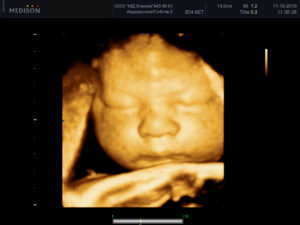

Объемное изображение лица плода на УЗИ

Оба вида УЗИ помогают в получении объемного цветного изображения. Однако, инновацией исследования в 4D-режиме является добавление координаты времени.

Это дает возможность транслировать сигнал в динамике со всех сторон плода — как в on-line, так и в записи.

При проведении Узи 4д при беременности вы увидите объемное и цветное изображение, и даже внешность вашего малыша с малейшими деталями.